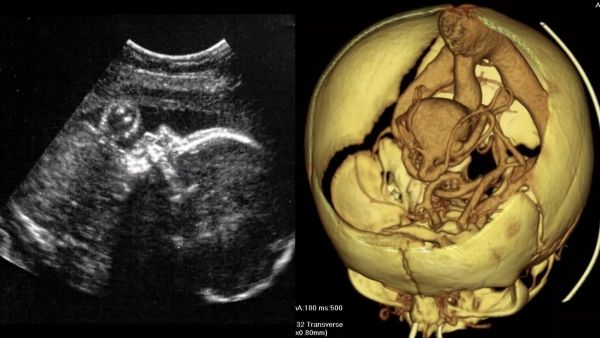

الاولى بالعالم.. اطباء يجرون جراحة لدماغ جنين في رحم امه

الاولى بالعالم.. اطباء يجرون جراحة لدماغ جنين في رحم امه قراءة المزيد »